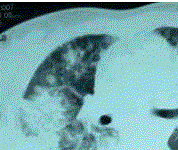

问题 患者女,23岁。间断发热伴皮疹1年半,诊断红斑狼疮。长期间断应用糖皮质激素治疗。近20 d来高热(T 39℃)伴咳嗽咳痰, CT(附图)示双肺满布圆形密度增高阴影,大小不等,密度不均匀,上、中肺野分布较多,双侧少量胸腔积液。血常规:WBC 2.52×10/L, N 0.62, Hb 92 g/L;ESR 40 mm/h;痰真菌培养:烟曲霉3次阳性;支气管镜检查右下叶、左舌段见黄色黏液性血性分泌物,毛刷找到霉菌孢子。 如果要确诊本病例,临床上需要

选项 A.半乳甘露聚糖(galactomannan,GM)检测阳性 B.除外肺部转移瘤 C.1,3-β-D-葡聚糖试验(G试验) 阳性 D.深部正常无菌组织培养发现曲霉生长或组织病理学检查发现曲霉菌丝 E.除外肺结核

答案 D